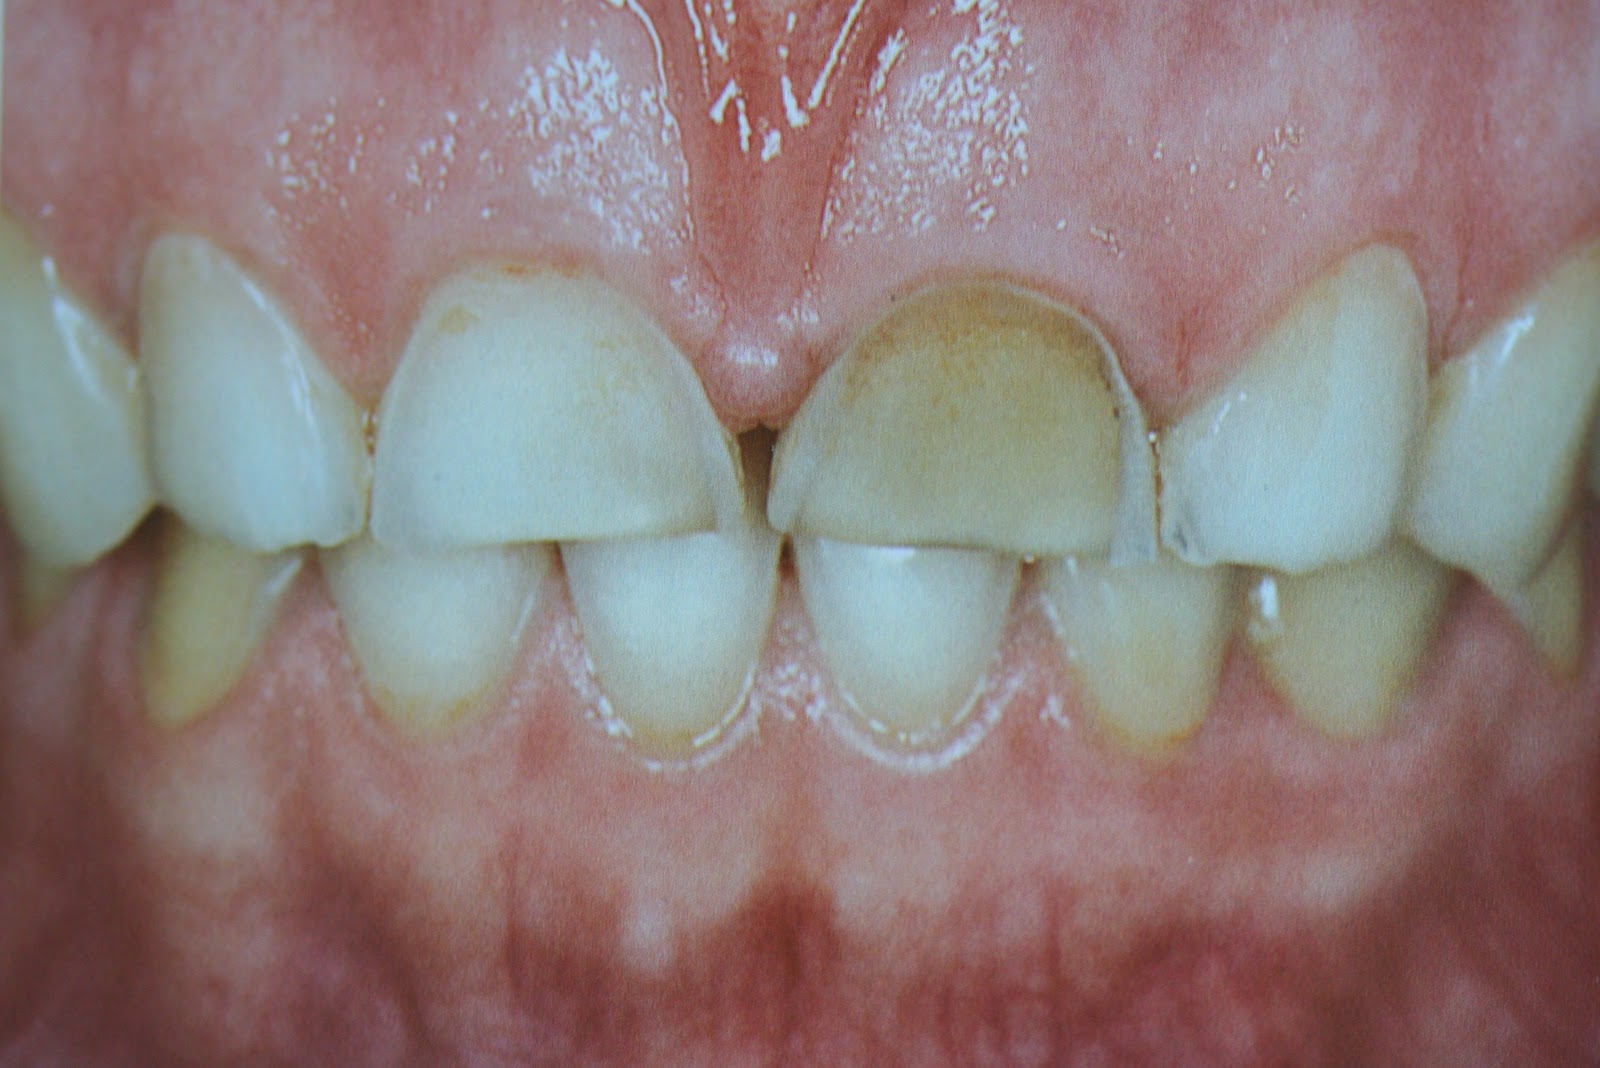

What Is Abrasion In Dental .   tooth abrasion is where your teeth start to lose enamel due to some sort of outside.  dental abrasion refers to the wearing away of tooth enamel, which is the hard outer layer of the tooth. It can occur due to various factors, such as. If you’ve noticed the signs of.   this condition, called dental abrasion, can occur when any foreign object causes friction against your teeth and gradually wears away the enamel on the surface. This wears away the enamel, the outer layer of the tooth, making it more susceptible to. However, bigger problems arise when your bite is out of alignment, often causing more friction in places less prepared for it.  tooth abrasion is a form of tooth wear that is caused by the repetitive grinding or scrubbing of the teeth against a hard surface. Dental abrasion is a condition that occurs when the tooth enamel wears away due to external factors. So, when two or more teeth come together, even with regular chewing with an ideal bite, some abrasion will occur. It can manifest as the loss of tooth structure, particularly.   abrasion is the result of repeated contact between a tooth and something hard, like teeth.

Dental abrasion is a condition that occurs when the tooth enamel wears away due to external factors.   this condition, called dental abrasion, can occur when any foreign object causes friction against your teeth and gradually wears away the enamel on the surface.  dental abrasion refers to the wearing away of tooth enamel, which is the hard outer layer of the tooth.   tooth abrasion is where your teeth start to lose enamel due to some sort of outside. So, when two or more teeth come together, even with regular chewing with an ideal bite, some abrasion will occur. However, bigger problems arise when your bite is out of alignment, often causing more friction in places less prepared for it.   abrasion is the result of repeated contact between a tooth and something hard, like teeth. If you’ve noticed the signs of. It can occur due to various factors, such as. This wears away the enamel, the outer layer of the tooth, making it more susceptible to.